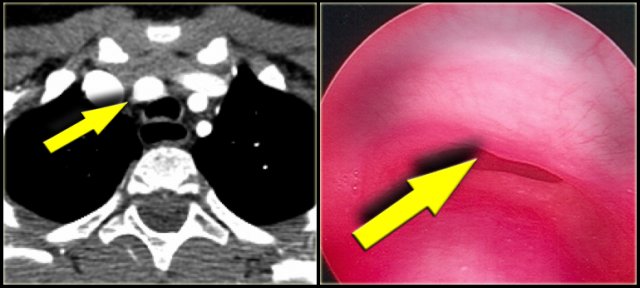

Dysphagia lusoria in patient with dilated aberrant right subclavian artery. Dysphagia lusoria in patient with dilated aberrant right subclavian artery.

Only rarely these patients become dysphagic (dysphagia lusoria) , when the origin of the right subclavian artery becomes dilated.

On a barium study of the esophagus you will see a posterior impression with an oblique course directed towards the right shoulder.

On the left a 78 year old woman with dysphagia.

There is consolidation in the right upper lobe, maybe due to aspiration.

There is a dilated vessel that compresses the esophagus and it originates from the left-sided aorta, i.e. an aberrant right subclavian artery.

On the left the same patient with dilated aberrant right subclavian artery.

Coronal reconstruction.